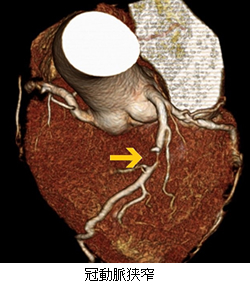

冠動脈CT検査(造影)

虚血性心疾患(狭心症や心筋梗塞)の確定診断をするための検査になります。

造影剤を腕の静脈から注入し、CT検査を行います。検査時間は15分程になります。